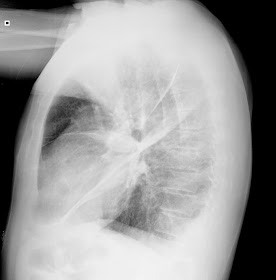

Aquí os dejo la imagen radiológica que acabo de ver en la guardia de hoy de un paciente monorreno (es decir con un solo riñón), con insuficiencia renal crónica  y con una Insuficiencia Cardiaca congestiva, en la que puede verse un tumor fantasma en el pulmón derecho:

Después de la primera sesión de diálisis ya no se ven los datos radiológicos de edema pulmonar pero se aprecia incluso mejor la imagen de líquido intercisural dando lugar al tumor evanescente o tumor fantasma.

Este paciente ya está estabilizado sin su edema pulmonar, ahora me queda mantenerlo estable hasta mañana por la mañana en la que se hará una nueva sesión de diálisis. Ya veremos entonces si desaparece completamente este líquido de la cisura pulmonar. Debería quedar como estaba hace 4 meses: